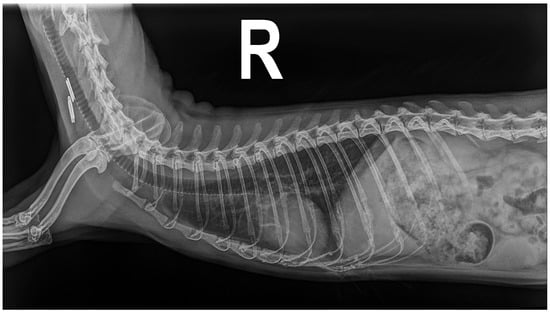

The best-positioned, standard 2-view thoracic radiographs (dorsoventral and right lateral projections) were obtained (HFQ-600P, Bennett, New Columbia, PA, USA). In the dorsoventral projection, tortuosity and dilatation of the caudal pulmonary arteries were observed, with a ratio of 1.21 between the ninth rib and the left caudal pulmonary artery. In addition, a mildly inverted D-shaped cardiac silhouette was observed, compatible with right ventricular enlargement [14]. In addition, a globose heart with a Vertebral Heart Score (VHS) of 6.5 (reference range 5.23 to 5.47) was noted in the right lateral projection [15]. A mild diffuse and bilateral pulmonary broncho-interstitial pattern was also reported. An electrocardiographic study (GE MAC 800, General Electric, Boston, MA, USA) was performed with the animal in the dorsoventral position, showing a sinus rhythm of the order of 180 bpm with a cardiac axis of 73°. No changes in electrocardiographic parameters were reported during the study [13].

A new radiological study was performed, and the dorsoventral projection showed a slight improvement in the tortuosity and dilatation of the caudal pulmonary arteries with a ratio of 1.08 between the ninth rib and the left caudal pulmonary artery. The inverted D-shaped cardiac morphology was also reported. The right lateral projection (Figure 3) confirmed the improvement of the pulmonary broncho-interstitial pattern and the reduction in the VHS to 5.5 [6,14,15]. An electrocardiographic study was repeated and showed a sinus rhythm of the order of 210 beats per minute with a cardiac axis of 74°, without pathological changes. The echocardiographic study performed during the evaluation of the animal showed the absence of parasites in the ventricles and vena cava, while a decrease in the velocity of tricuspid regurgitation (2.8 m/s) and a decrease in the diameter of the atrium, ventricle, and pulmonary trunk were demonstrated (Table 1) [8,13].

Figure 3. Radiological study in right lateral projection of the ferret 35 days after extraction of the adult parasites of Dirofilaria immitis.